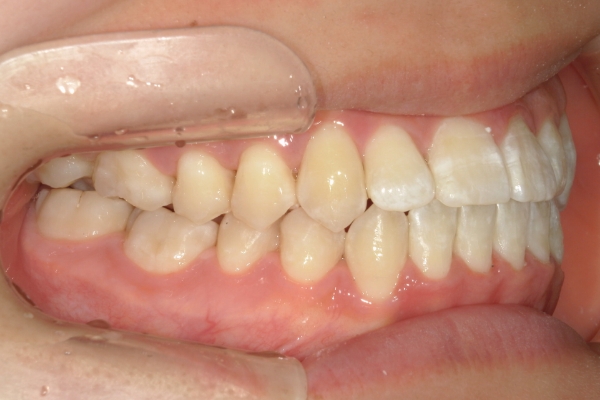

BEFORE

治療前

PROCESS

3か月

AFTER

治療後

骨格的に下あごが前下方に長いことが原因で、受け口、開咬(前歯が当たらない)の症状がでていました。また下あごが右にずれており、その影響で上下の歯列正中(真ん中)の大きなずれも生じていました。顎変形症手術も選択肢の一つでしたが、患者さまの希望もあり、下顎左側小臼歯の抜歯をして通常の歯列矯正で治療をしました。

前歯、奥歯の噛み合わせが大きく改善され、上下の歯真ん中が一致しました。食べ物が噛みやすくなったこともですが、歯列の見た目が整った点にも患者さまは満足されていました。